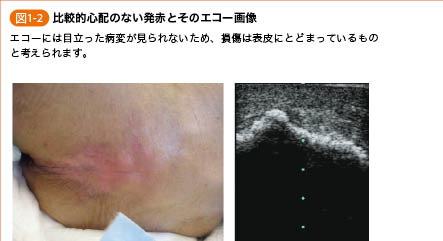

はじめての褥瘡エコー 前編 かんかん! -看護師のためのwebマガジン by 医学書院。

はじめての褥瘡エコー 前編 かんかん! -看護師のためのwebマガジン by 医学書院。

はじめての褥瘡エコー 前編 かんかん! -看護師のためのwebマガジン by 医学書院。

はじめての褥瘡エコー 前編 かんかん! -看護師のためのwebマガジン by 医学書院。